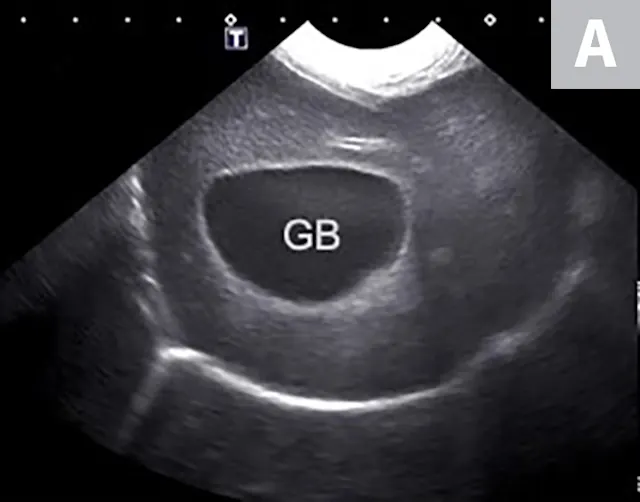

Imaging of a 1-year-old neutered male standard poodle presented with anorexia, lethargy, vomiting, hypoalbuminemia, hypoproteinemia, and cranial abdominal organomegaly. Transverse (A) and sagittal (B) ultrasound of the liver and gallbladder (GB). The liver is enlarged (with increased distance off the stomach from the diaphragm, rounded borders, and extension ventral to the stomach), diffusely hyperechoic, and homogenous. The gallbladder is moderately distended with a normal wall and content. Radiographs demonstrate hepatomegaly and splenomegaly (C). Abdominal ultrasound images revealed splenic enlargement with a mildly mottled architecture and a solitary hypoechoic nodule (D; arrowheads). The pancreas is enlarged and lobulated with multiple hypoechoic tracts and a peripheral capsule (E; between electronic cursors [X’s]). The jejunal lymph nodes are severely enlarged (F; between electronic cursors [X’s]), more than expected for a young dog. The combination of severe hepatosplenomegaly and lymphadenomegaly make systemic disease (eg, infectious, neoplastic) most likely. The appearance of the pancreas is due to pancreatic edema secondary to hypoproteinemia. Acute liver injury was diagnosed, and lymphoma was diagnosed based on hepatic and splenic cytology.